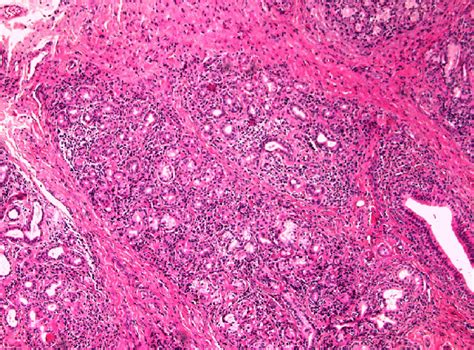

Spotting adenocarcinoma early is key, and knowing the potential symptoms is your first line of defense. The tricky part is that symptoms often vary widely depending on the location of the cancer. For example, lung adenocarcinoma might cause a persistent cough, shortness of breath, chest pain, or coughing up blood. Colon adenocarcinoma can manifest as a change in bowel habits (diarrhea, constipation), blood in the stool, abdominal pain or cramping, unexplained weight loss, or fatigue. If it’s in the breast, you might notice a new lump, skin changes, or nipple discharge. Pancreatic adenocarcinoma can present with jaundice (yellowing of the skin and eyes), abdominal or back pain, unexplained weight loss, loss of appetite, and changes in stool. Stomach adenocarcinoma might cause indigestion, heartburn, nausea, vomiting, or a feeling of fullness. The diagnosis process usually starts with a thorough medical history and physical examination. If a doctor suspects cancer, they’ll likely order imaging tests like CT scans, MRIs, or PET scans to visualize the tumor and see if it has spread. Blood tests, including tumor markers, can sometimes provide clues. The definitive diagnosis, however, almost always requires a biopsy. This involves taking a small sample of the suspicious tissue, which is then examined under a microscope by a pathologist. They can confirm if it’s adenocarcinoma, determine its grade (how aggressive the cells look), and identify the specific type. Sometimes, endoscopic procedures (like colonoscopy or bronchoscopy) are used to access and biopsy tissues. Early detection through regular screenings and being aware of your body are absolutely critical, guys.